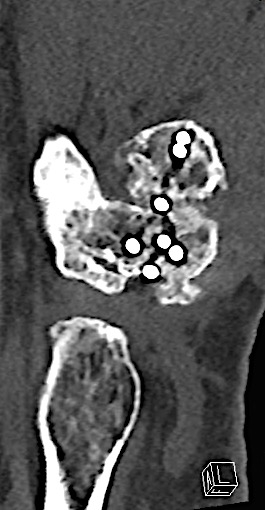

Case 3:

A 60-year-old male patient required an arthrodesis of the thumb carpometacarpal (CMC) joint after an implant arthroplasty in conjunction with the implantation of cortico-cancellous bone graft following a proximal row carpectomy and a previous arthrodesis between trapezium-trapezoid and the 2nd CMC joint (Fig 9). The first metacarpal dorsal plate from the VA Locking Hand System was selected for the procedure (Figs 10 - 11).